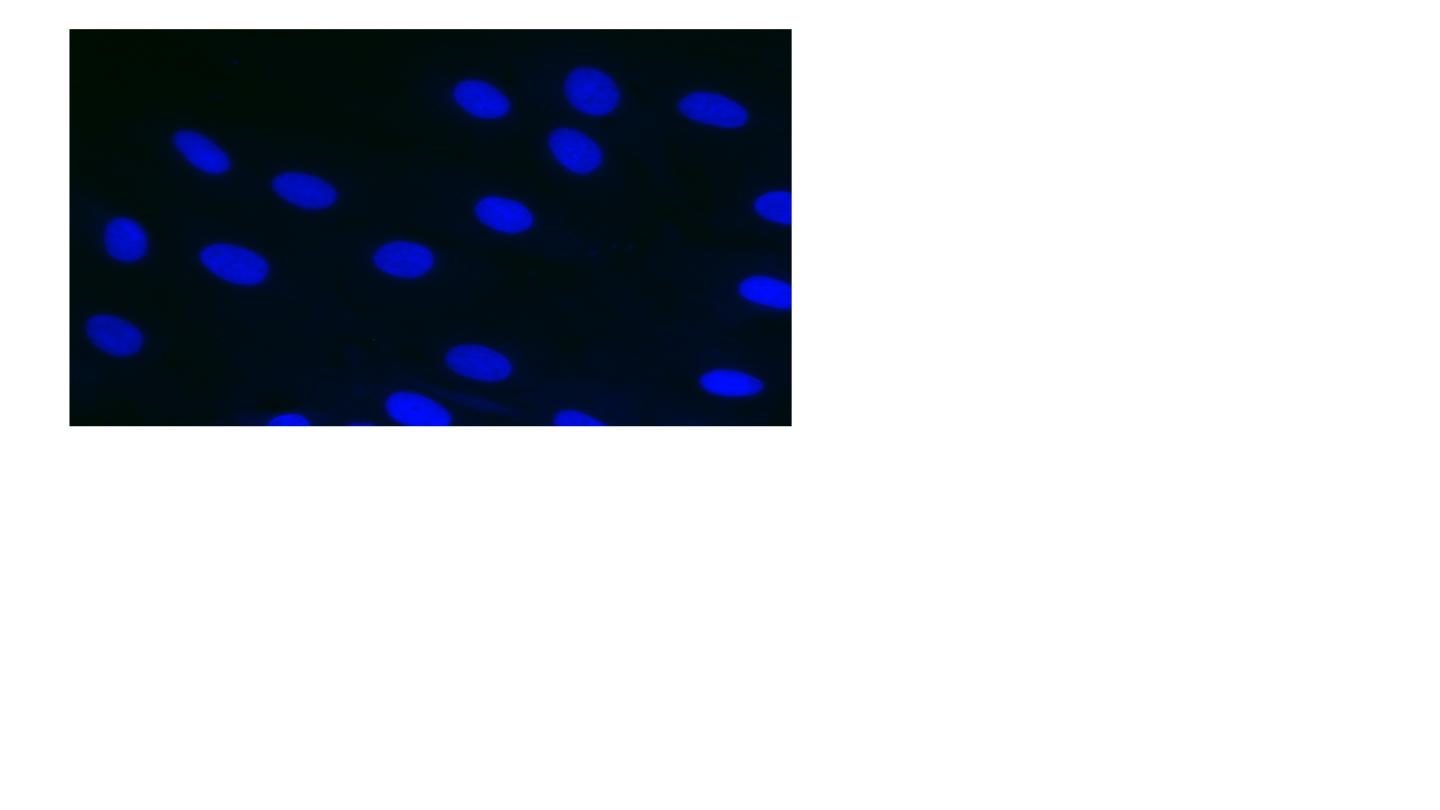

image: The images show DM1 cells, untreated and treated with kinase inhibitors. Following treatment with inhibitors targeting CDK12 nuclear foci in DM1 cells are reduced.

In this new study, scientists have discovered that through the inhibition of the molecule CDK12 - the additional faulty RNA disappears, and so reduces the symptoms of the condition.